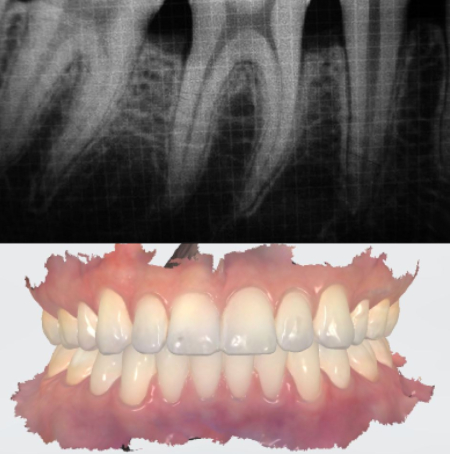

Dental X-rays

Dental X-rays & 3D Scans

We use state-of-the-art dental X-ray and 3D Scan technologies to get a detailed view of your teeth, bones, and gums. This helps us accurately diagnose dental issues, such as cavities, bone loss, and impacted teeth, ensuring a precise treatment plan for your oral health.